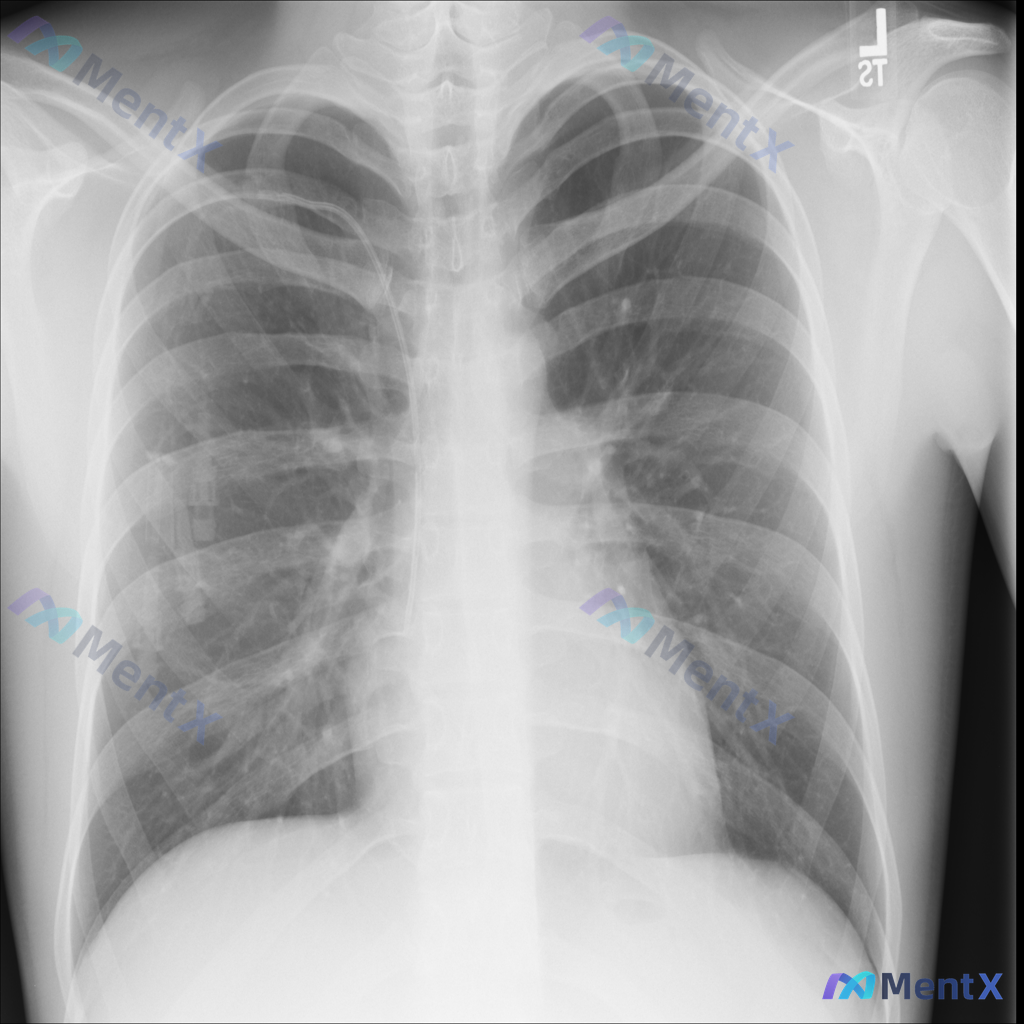

整理了一份床旁胸片的分析资料,大家可以先看看核心线索,讨论下第一眼的思路。 基础情况:影像为床旁前后位胸片,右侧肺野可见管路影,右侧腋下有电极片伪影。 核心影像发现: 1. 右肺野中上部(接近第3-4前肋间)可见一较明显的类圆形高密度结节影,边界相对清晰 2. 右侧胸壁/肺野有管路影(提示可能为深静...